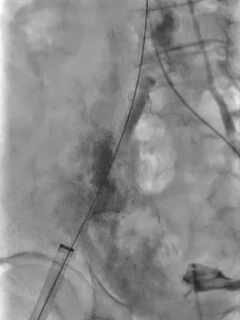

根部造影,可见大量反流

第一次展开,瓣膜形态敞口

第二次展开,瓣膜位于0位;此时患者发生室颤,除颤后进行按压

瓣膜按压后位置发生变化

多体位观察

瓣膜位于瓣上,选择回收

再次定位释放

大弯侧0位,形态可见压缩

小弯侧深度尚可

瓣膜脱钩,轻微自同轴

脱钩后造影,瓣膜稳定,无反流

左侧位造影,小弯侧深度尚可